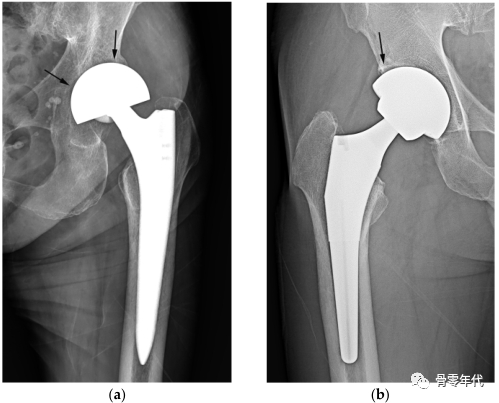

半关节置换术(a)和全髋关节置换术(b)的简单x线片。双极半关节置换术(a)中,髋臼软骨下骨板和相邻关节间隙(箭头)得以保留,髋臼杯外表面光滑而非粗糙(箭头)。杯子的弦线(红线)偏离球体的直径。在THA (b)中,软骨下骨终板和软骨间隙缺失(箭头),杯和骨之间的界面光滑,显示出外部球形轮廓的细微压痕(箭头)。杯子的弦线(红线)接近球体的直径(黑线)。在这两幅图像中,黑线表示球体的直径,而红线表示连接髋臼杯或双极头的内外边缘的弦线。